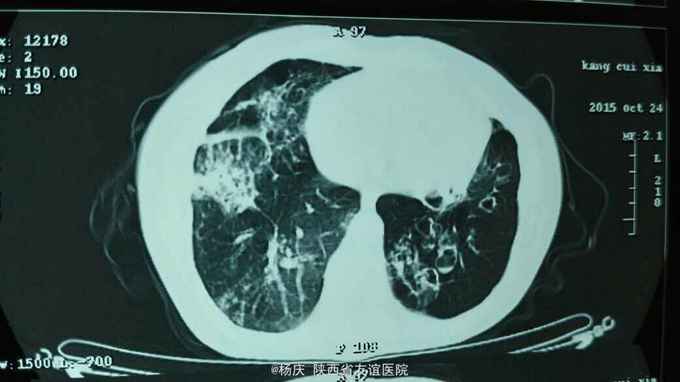

咳嗽,咳痰40年,加重1周,发热1天 40年前始反复咳嗽,咳痰,间断咯血,无声嘶、消瘦。反复多次影像学检查诊断:支气管扩张。1周前上述症状再次发作,外院静脉输液"克林霉素"常规量5天,疗效不佳。1天前出现发热,体温40.0摄氏度,发热前无发冷寒战。今被收住我院,自发病来,精神尚可,大小便正常。 既往无特殊疾病史。

TPR:39.0 80 20。血压120/80mmHg。口唇紫绀,桶状胸,双肺扣呈过轻音,双肺密集湿性啰音。心腹查体无异常。双下肢不肿。

支气管扩张并感染